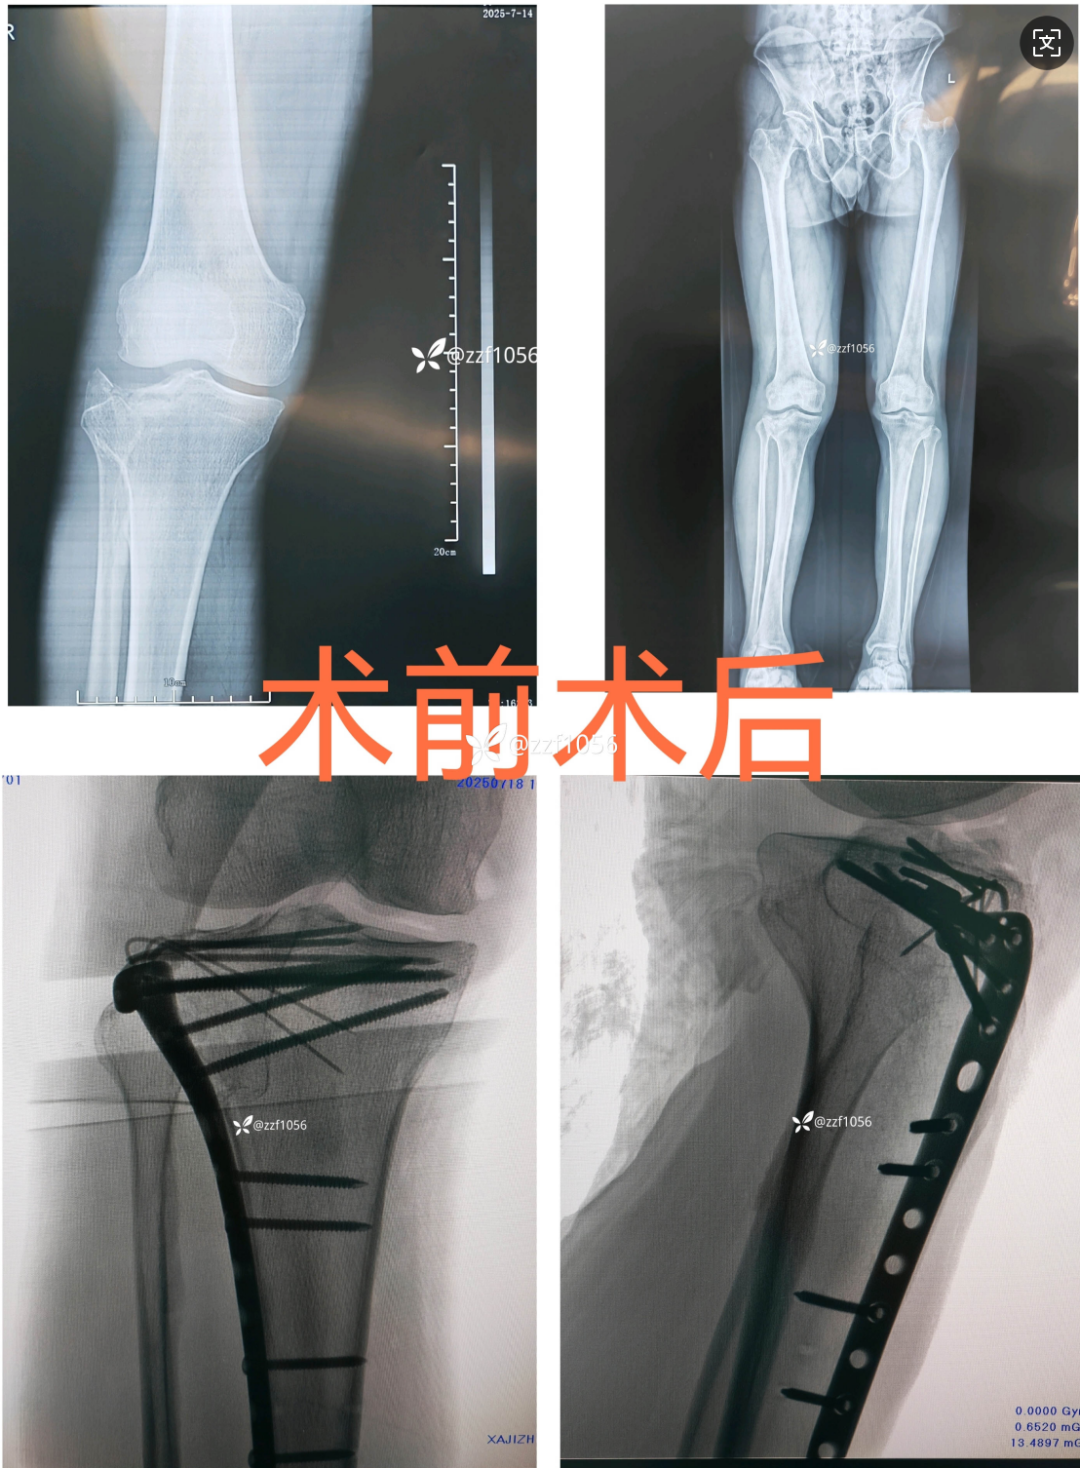

患者诊断为右侧胫骨平台骨折,I 类切口,行切开复位钢板内固定术。

手术前后 X 片: